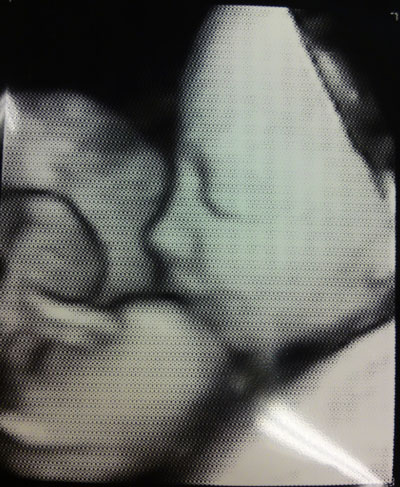

Sitten jälleen asetuin siihen pöydälle, ja lääkäri otti jopa niitä 4-D-kuvia. Nyt on kiva kasvokuvakin toisesta lapsesta nöpönenineen. Saimme kaksi kuvaa, tässä toinen niistä.